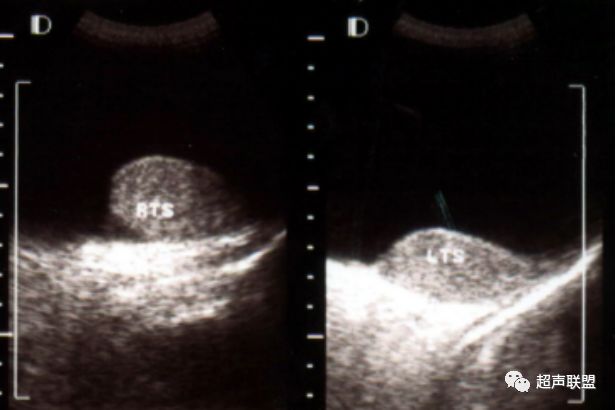

节段性睾丸梗塞 令人尴尬的 楔形 华斌的超声世界 二十次幂